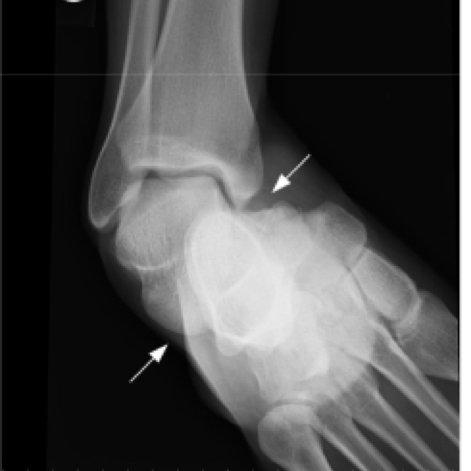

Xray of dislocation:

It's not uncommon for a peroneal tendon dislocation to be associated with an ankle dislocation, where essentially the tibia slips off the talus. This puts significant pressure on the lateral ankle where the peroneal tendons sit.